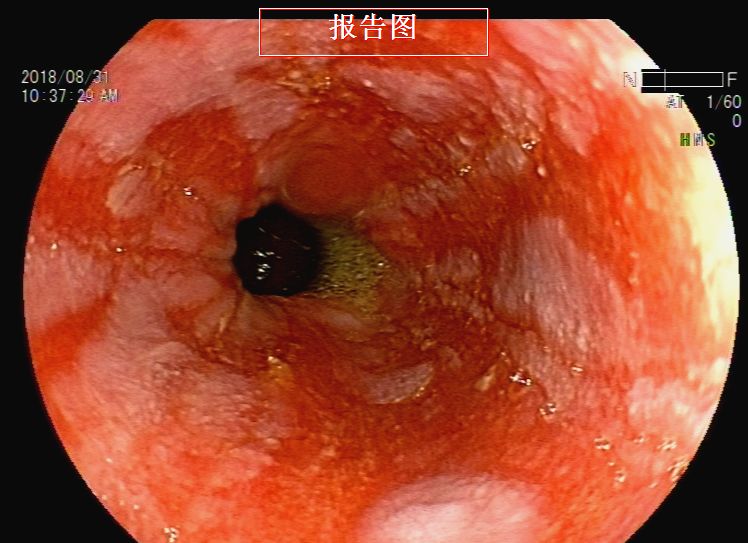

胃镜检查:反流性食管炎,胃内液体潴留,吻合口前区黏膜下隆起——考虑转移灶压迫,近端小肠梗阻(图9、图10、图11、图12、图13)。根据消化道造影及内镜检查结果,考虑梗阻部位在近端小肠,吻合口前区虽有较大的隆起灶,但是内镜通过可,暂不处理。

图9 胃镜检查见反流性食管炎